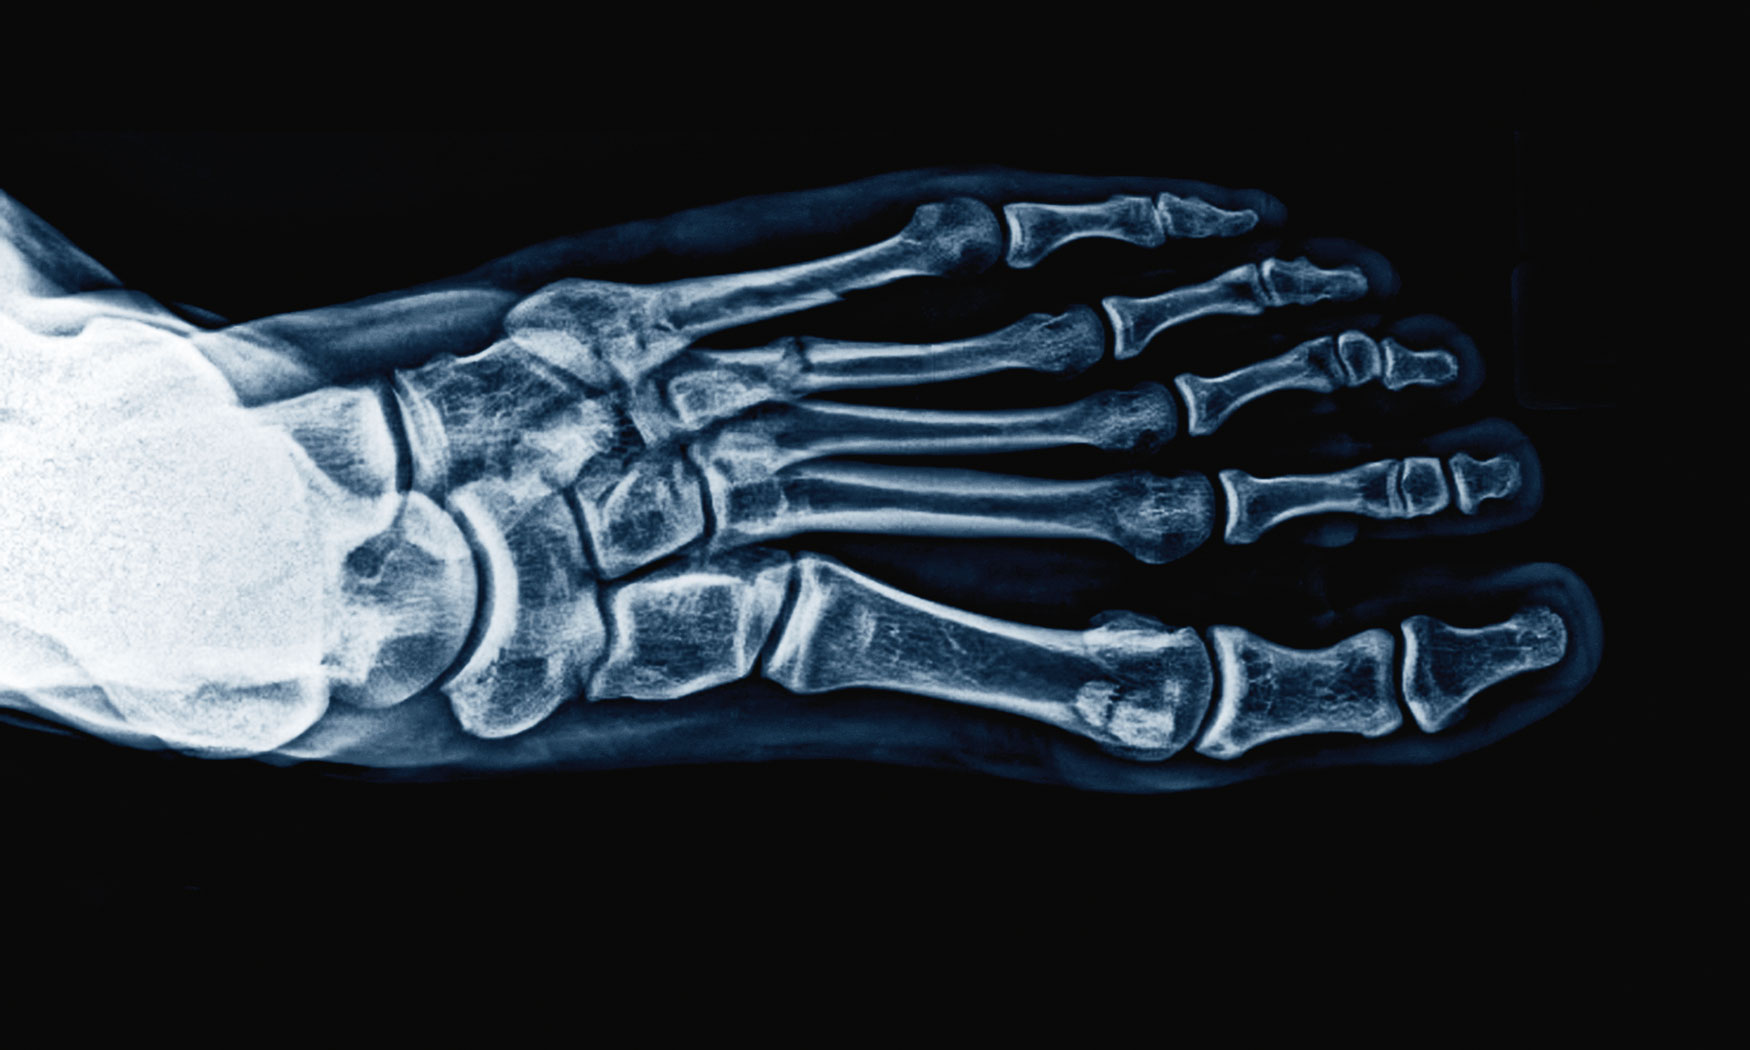

Złamanie zmęczeniowe kości śródstopia. Złamanie zmęczeniowe kości śródstopia. materiały prasowe

ŁUKASZ CHOJECKI: – Nie ma precyzyjnej odpowiedzi. Stopa składa się z 26 kości i aż 33 stawów, ale ludzie mają różną budowę anatomiczną, elastyczność i historię urazów. Ciało potrafi dostosować się do stopniowo zwiększanych obciążeń. Po miesiącach pracy w biurze można się wybrać na wędrówkę w góry i wrócić z co najmniej lekkim bólem stopy, a u regularnie trenujących sportowców stopa i staw skokowy są w stanie wytrzymać wielomiesięczne przygotowania i start w maratonie ulicznym, a nawet przebiec 230 km przez Saharę podczas „Marathon des Sables”. Ta zdolność dostosowania wynika z tzw. prawa Wolfa, które mówi, że kość ulega wzmocnieniu, czyli uwapnieniu, pod wpływem sił mechanicznych. Obciążanie jest jednym z głównych czynników stymulujących jej tworzenie.